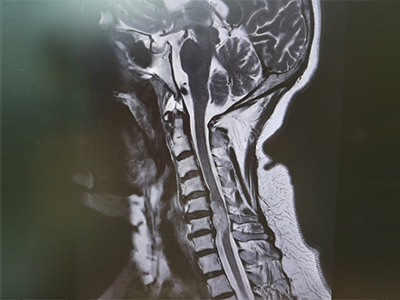

脊柱脊髓神經(jīng)微創(chuàng)中心以微創(chuàng)技術(shù)為引領(lǐng),以功能恢復(fù)為目標(biāo),主要治療脊柱外傷、腫瘤、退行性病變、脊柱畸形等疾病。團(tuán)隊(duì)利用神經(jīng)外科顯微技術(shù),結(jié)合神經(jīng)內(nèi)鏡微創(chuàng)技術(shù),對(duì)脊柱間盤變性疾病、頸腰椎管狹窄、頸腰椎間孔狹窄、頸腰椎間盤突出、頸腰椎體不穩(wěn)、脊柱骨折、寰樞椎脫位、脊柱腫瘤、椎管內(nèi)腫瘤、脊髓損傷、脊髓空洞、脊髓栓系等疾病進(jìn)行高效、特色手術(shù)治療,如顱頸交界區(qū)畸形寰枕減壓內(nèi)固定術(shù)、脊柱腫瘤全脊椎切除內(nèi)固定術(shù)、微創(chuàng)椎管內(nèi)腫瘤切除術(shù)、微創(chuàng)脊柱旁腫瘤切除術(shù)、寰樞椎脫位椎間融合內(nèi)固定術(shù)、脊柱骨折微創(chuàng)經(jīng)皮椎弓根釘內(nèi)固定術(shù)、經(jīng)椎間孔椎間融合內(nèi)固定術(shù)(MIS—TLIF)等,最大程度降低脊柱脊髓手術(shù)創(chuàng)傷,具有創(chuàng)傷小、輸血少、恢復(fù)快、口碑好,出院早等優(yōu)勢(shì)。